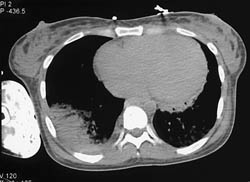

Diagnosis

Lisfranc Fracture - See Tarsal Metatarsal Row